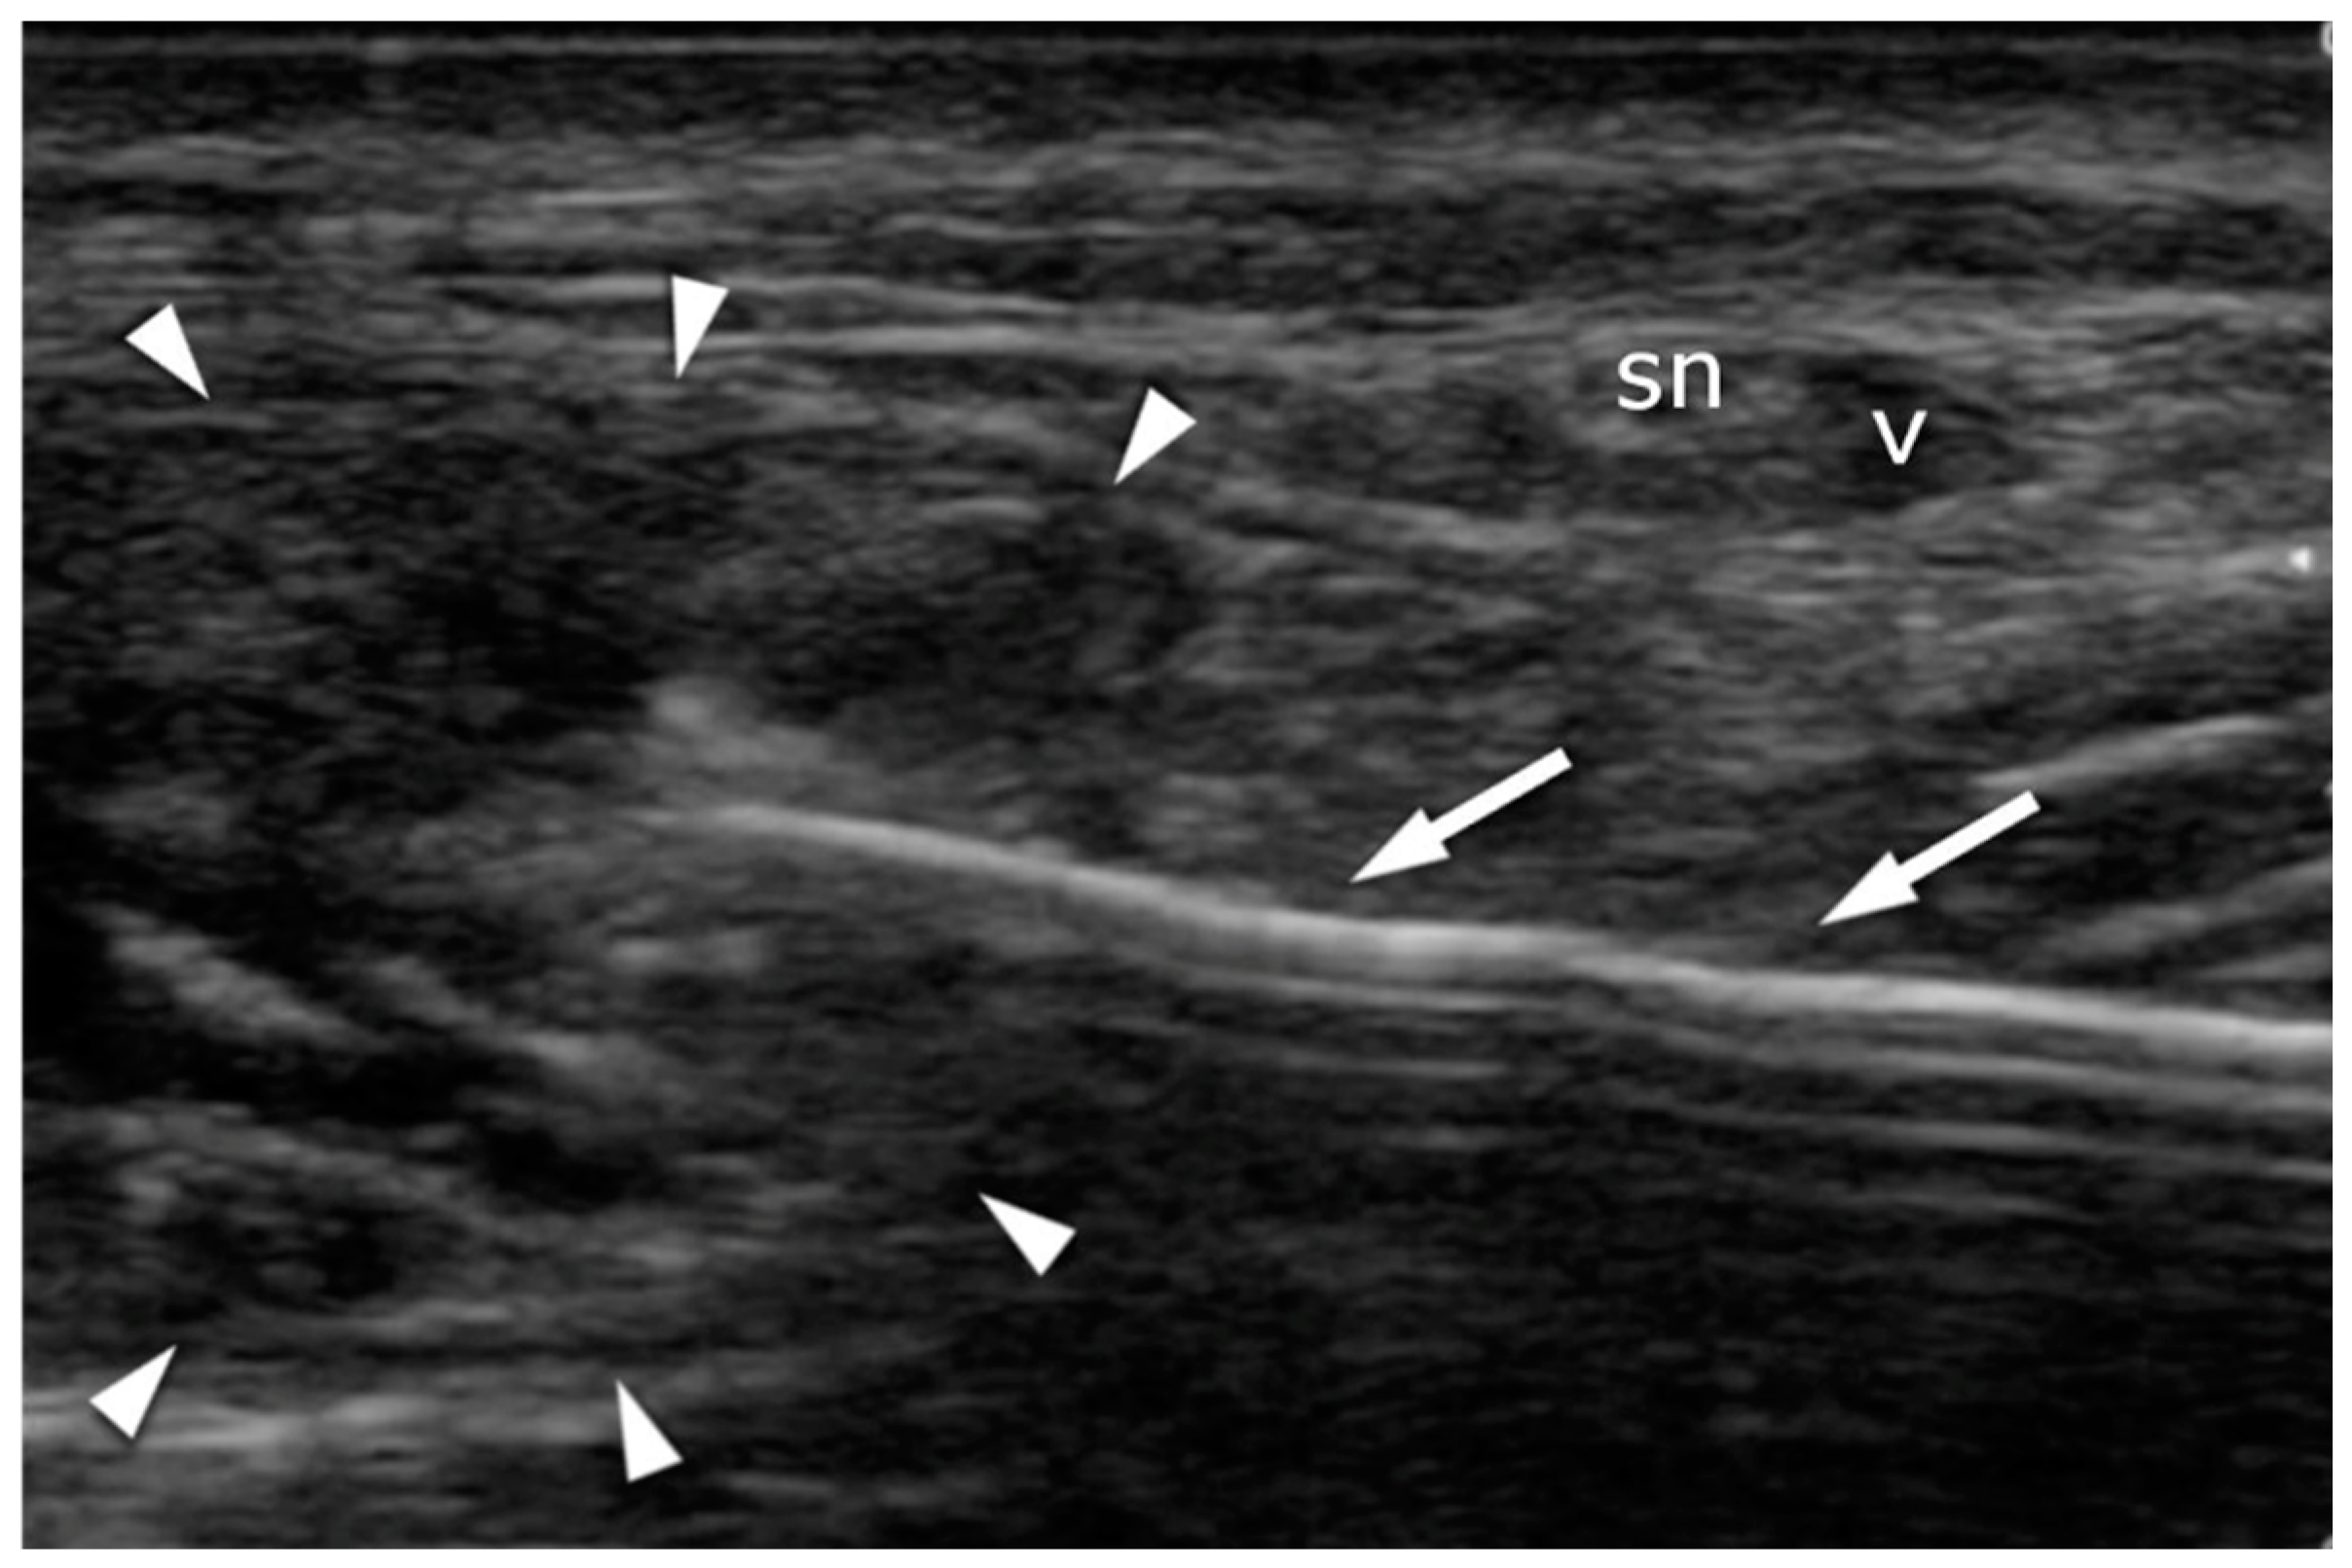

A high-resolution real-time ultrasound examination was performed in the operation room. We used a sterile draped high-frequency (10–12 MHz) linear probe. Transverse scans were used to localize the SN. It was followed from the proximal area of the calf—where it laterally follows the saphenous vein in its fascial compartment between the two heads of the gastrocnemius—to the distal area and the lateral malleolus area. The SN’s echogenicity is oval and typical of nerves, showing hyperechogenic spots in the hypoechogenic area surrounded by the hyperechogenic sheath (Figure 5, Supplementary Material Video S1). The entry point and the angle of the needle were chosen with direct US guidance (Figure 6, Supplementary Material Video S2). The suture course was checked before it entered the skin incision (Figure 7, Supplementary Material Video S3).

Figure 6.

Achilles tendon (arrowheads) suturing: transverse plane. The needle (arrows) is introduced under US guidance in order to avoid contact with the sural nerve (sn) and the vein (v).